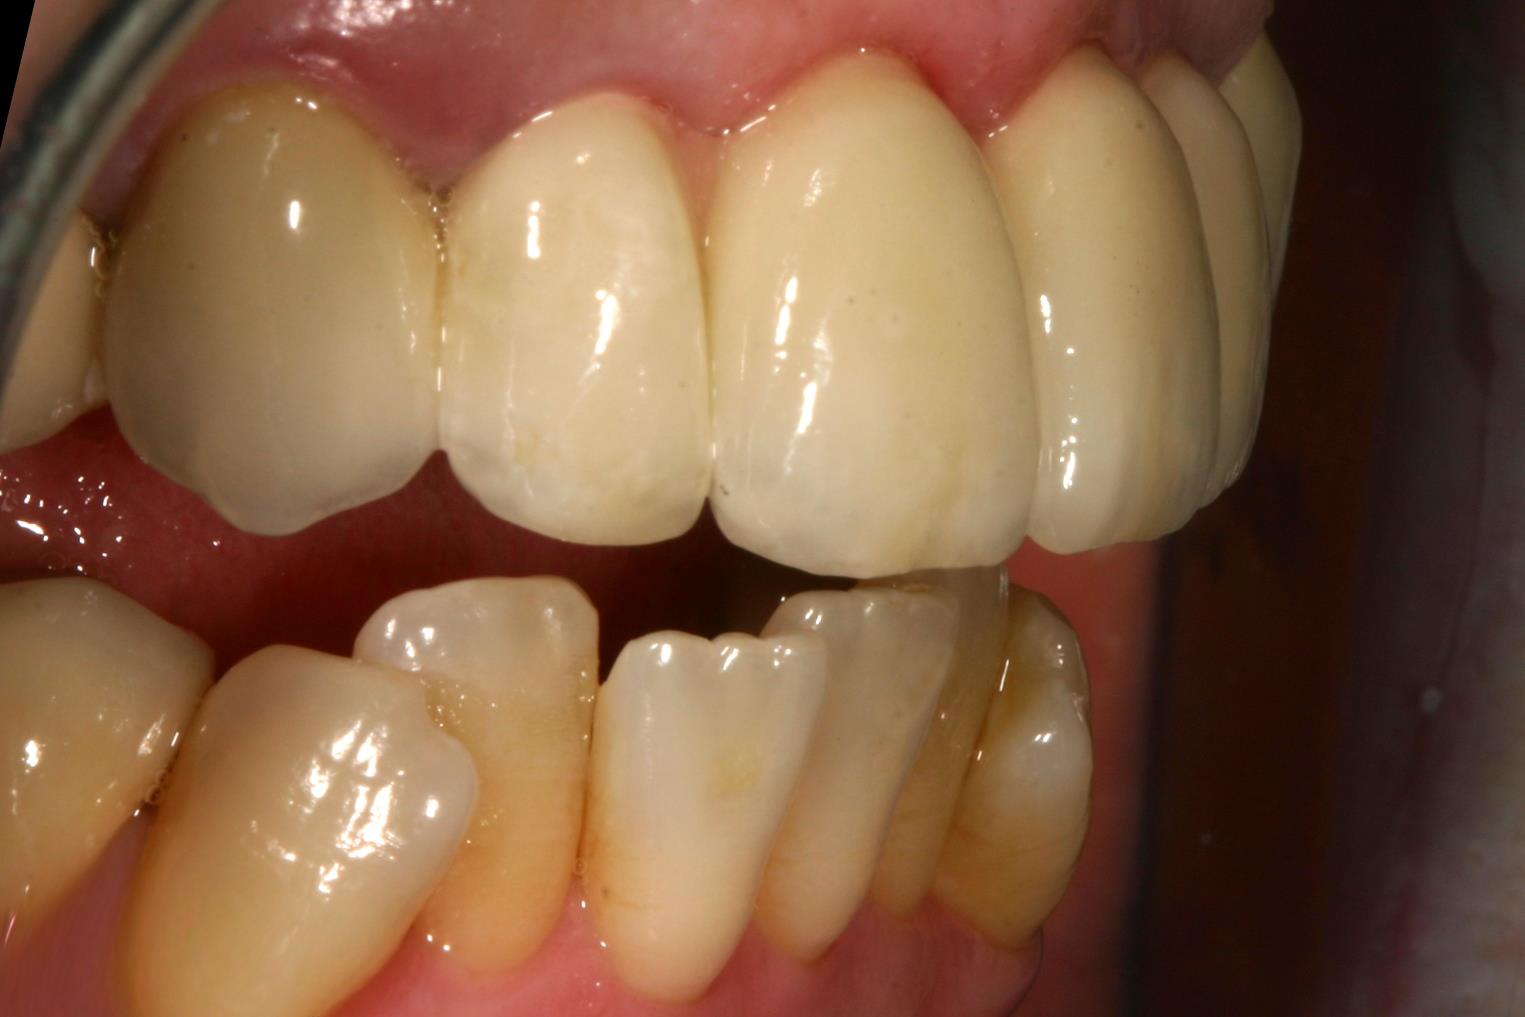

Vollkeramik kontra Metallkeramik